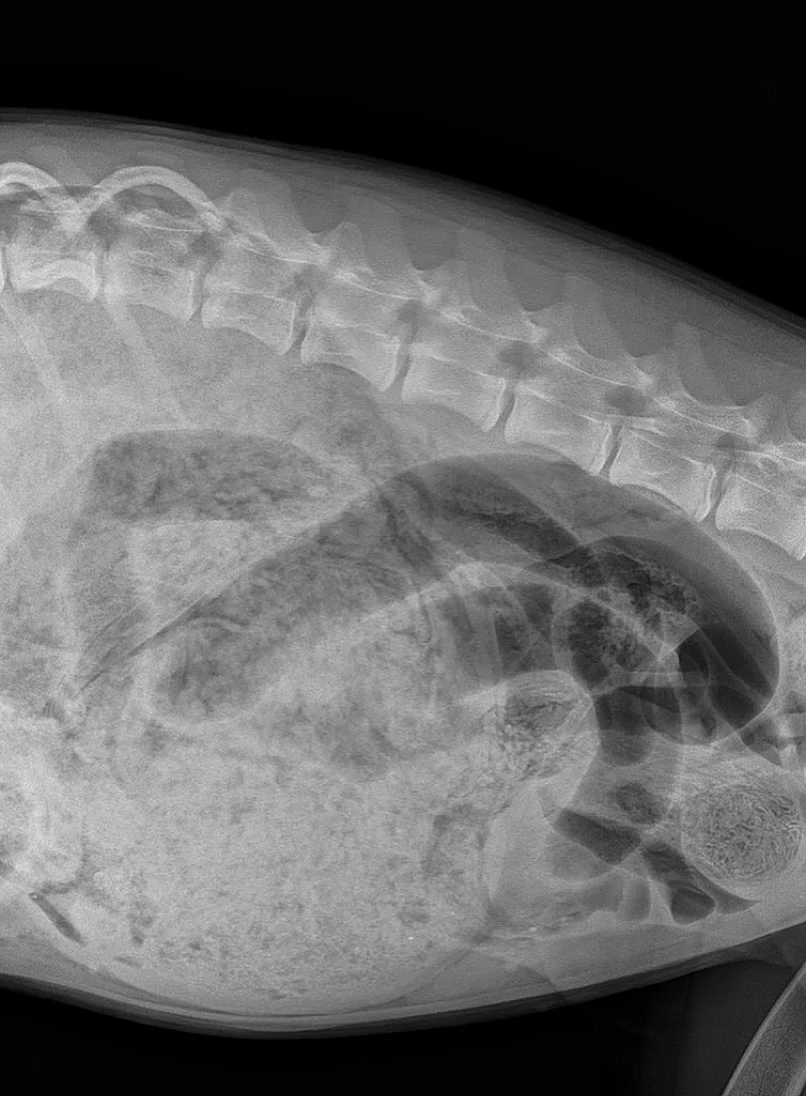

במהלך הבדיקה הבחינו הווטרינרים כי בטנה של לונה נפוחה. הם ערכו סריקת רנטגן וגילו שבטנה של לונה מלאה בעצמים זרים שגרמו לה לחסימת מעיים. הם מיהרו להכין את הכלבה לקראת ניתוח חירום מציל חיים.

מתברר כי לונה השובבה בלעה שורה שלמה של פריטי לבוש: וואנזי, סוליית נעליים, גומיות שיער ולא פחות מ-24 גרביים.